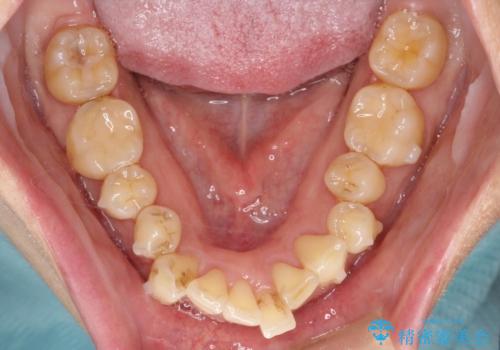

- 全体的なガタガタと前歯をきれいにしたいとのことで来院されました。

下の歯は重度のガタガタがあり、上の前歯は何本かが神経の治療がしてある状態でした。

インビザラインにて歯並びを整え、上顎の前歯にセラミックを装着する計画としました。

セラミックと矯正を組み合わせることにより、審美的にも機能的にも改善することができました。